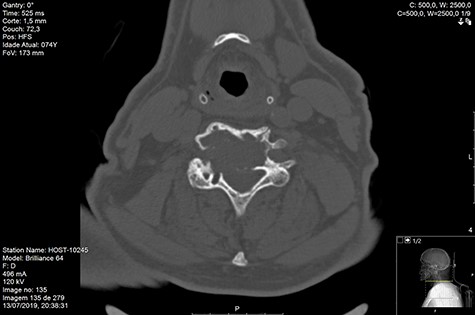

Computed tomography (CT) (Figs 1–3) and magnetic resonance imaging (MRI) (Figs 4–6) of the cervical spine were performed and revealed a lytic lesion involving most of C4, C5 and C6 vertebral bodies with bilateral extension to the posterior spinal elements of C4 and C5 and complete disruption of C4-C5 and C5-C6 intervertebral discs.

The Spinal Instability Neoplastic Score (SINS) [4, 6, 7] for assessing spinal instability from metastatic disease was used and the lesion was deemed unstable (SINS 13), with impending risk of increased neurological damage.

Findings from laboratory tests (serum protein electrophoresis) led to the diagnosis of MM. The patient was placed on a Philadelphia c-spine collar and underwent local 3D external-beam radiotherapy (20Gy in five fractions).